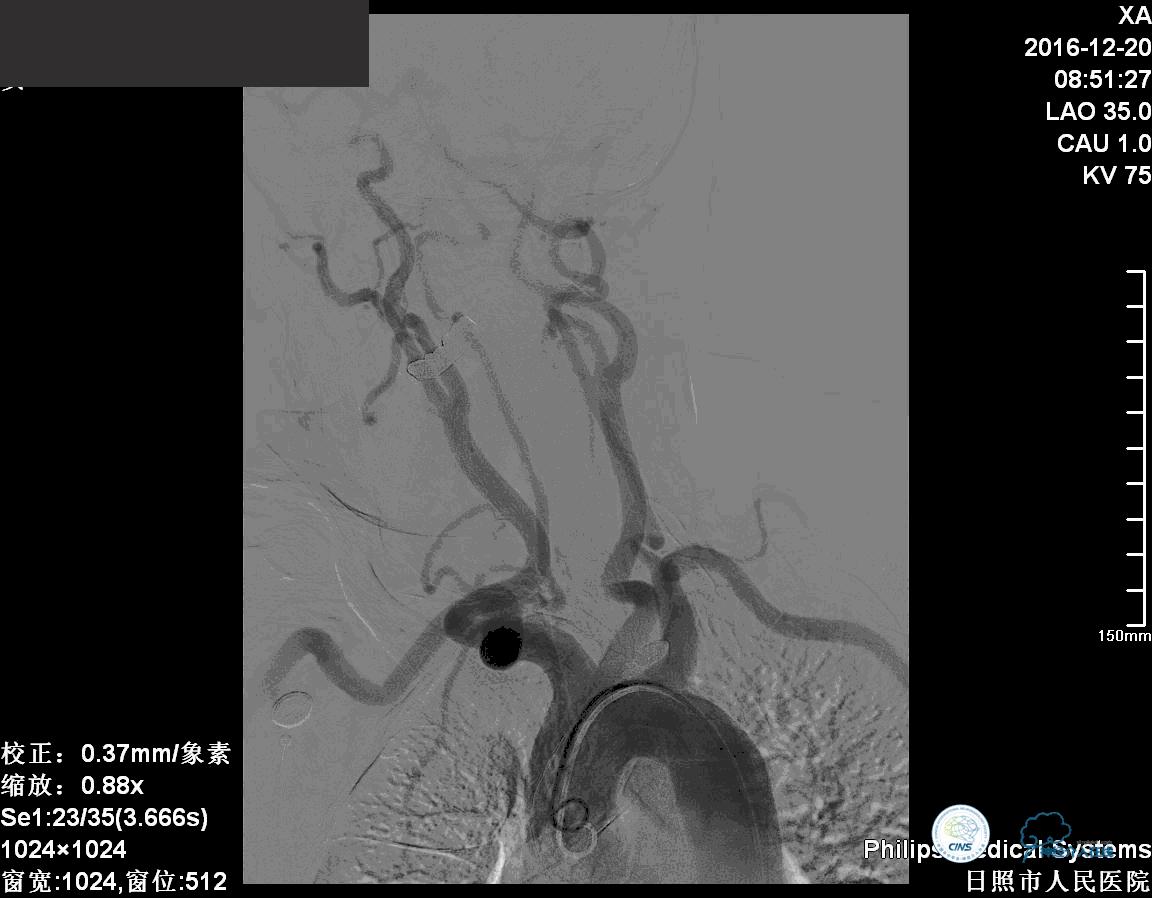

确诊:基底动脉顶端宽颈未破裂动脉瘤,动脉瘤大小约6mm×9mm,瘤颈约4毫米。

对于这个动脉瘤的介入治疗措施,包括球囊辅助弹簧圈栓塞介入治疗、支架辅助弹簧圈栓塞介入治疗、双微导管技术弹簧圈栓塞介入治疗。

这个病例我们采取了双微导管技术弹簧圈栓塞治疗。

我们将两个微导管分别送入动脉瘤腔内,其中一个塑为u型,一个直头。两个微导管,一个位于动脉瘤较深的部位,1个位相对较浅的部位,交替进行栓塞。

前两个弹簧圈对动脉瘤的瘤颈和动脉瘤的后部进行了栓塞。成篮稳定以后,开始对动脉瘤的内部和前部进行栓塞。